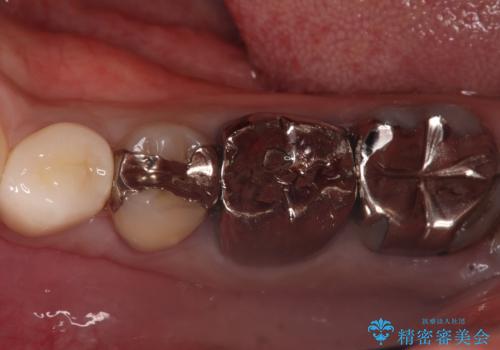

歯と歯の間の虫歯もセラミックで再発防止

担当医 河口智英